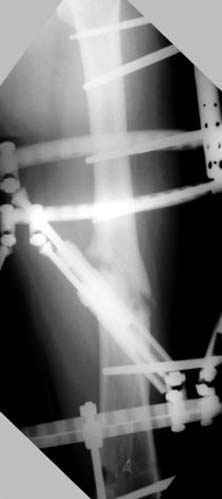

Несколько снимков из моей коллекции, чтобы разьяснить, почему мы до сих пор делаем различные варианты остеотомии.

На рисунке N1 предоперационный план лечения ложного сустава шейки бедра- линия ложного сустава, угол и направление введения импланта, клиновидная остеотомия в градусах и миллиметрах, второй снимок после коррекции, расчет, на сколько удлиняется конечность и размеры импланта;

N3 рисунок окончательный снимок, после операции моя рентгенограмма должен выглядеть примерно как эта картина. На N4 снимке клин перед удалением; N5 послеоперации 3 нед.; N6 окончательная рентгенограмма.

(доложен в Ст. Петербурге 2003 и в Москве 2004)

варус при проксимальном отделе 95 градусной пластиной.

пластическая модель; и коррекция бедра аппаратом Илизарова.